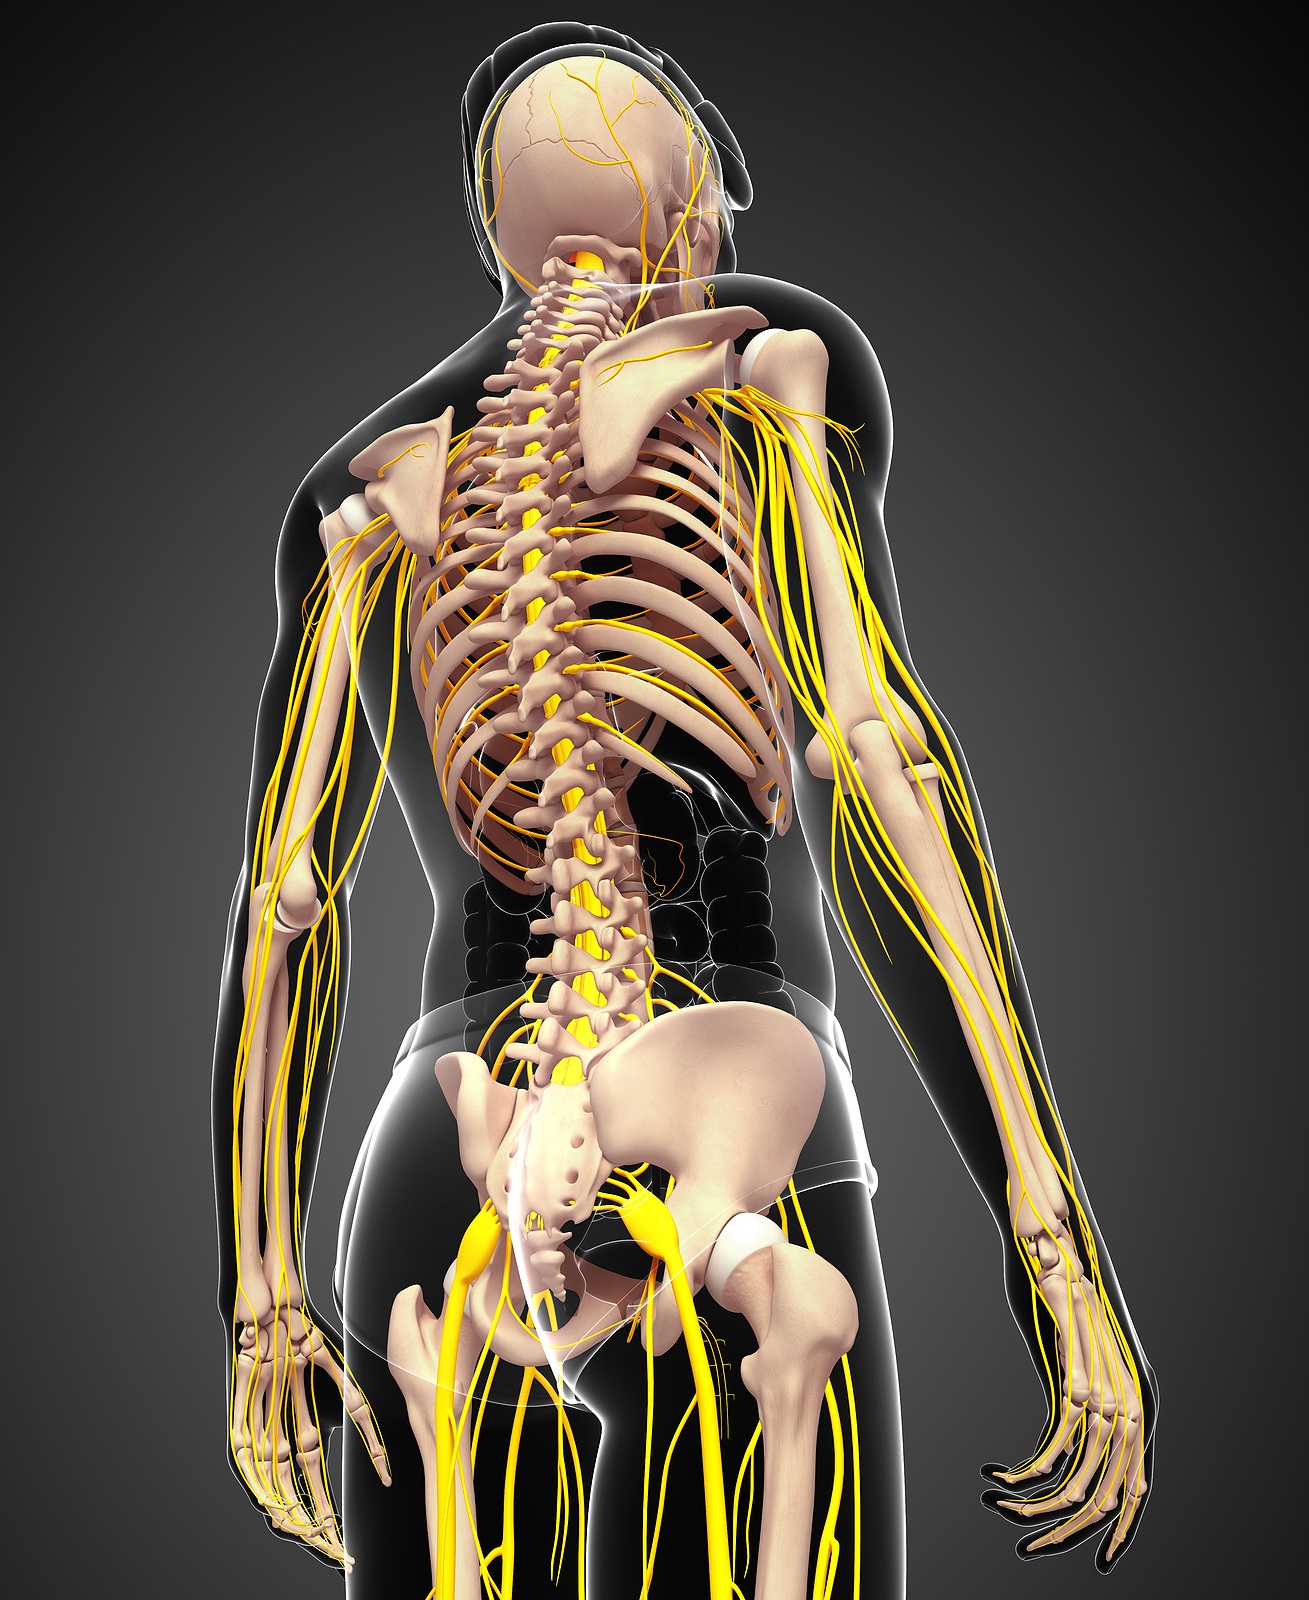

The spinal cord originates at the base of the brain and travels down the spine through the hollow tube formed by the vertebral arches into the L2 vertebra. Below this level is a bundle of nerves that further extend downward and travel to the pelvic organs and lower limbs. This bundle of nerves is called the cauda equina. In Latin, this term means ‘horse’s tail’ because it resembles the strands of a horse’s tail.

The spinal cord also consists of nerve roots that extend from the sides of vertebrae. Networks of nerve roots allow long nerve fibers to travel throughout the body and form the body’s electrical system. The nerve roots and fibers along the cervical spine extend to the neck, shoulders, arms, and hands. The nerves in the thoracic spine travel into the chest and abdomen. Nerve roots that originate in the lumbar spine consist of nerve fibers that travel to the lower regions of the body such as the pelvis, hips, thighs, legs, and feet.